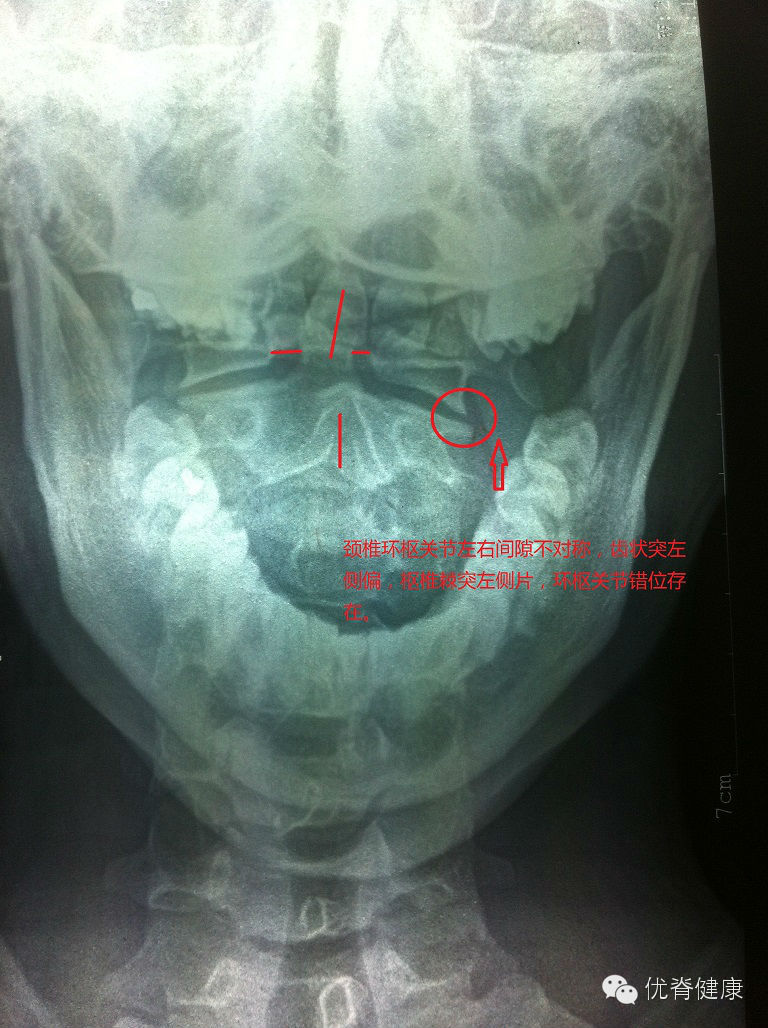

环枢关节错位,颈椎生理曲度反弓,轻度右侧弯,部分骨质增生;腰椎轻度左侧弯,伴骶椎S1隐裂;颈腰部肌群不同程度劳损,以上颈部及下腰部肌群劳损较为明显。

评估分析:颈椎软组织劳损,伴环枢关节错位,颈椎生理曲度反弓,伴轻度右侧弯。腰椎轻度左侧弯,腰肌劳损。